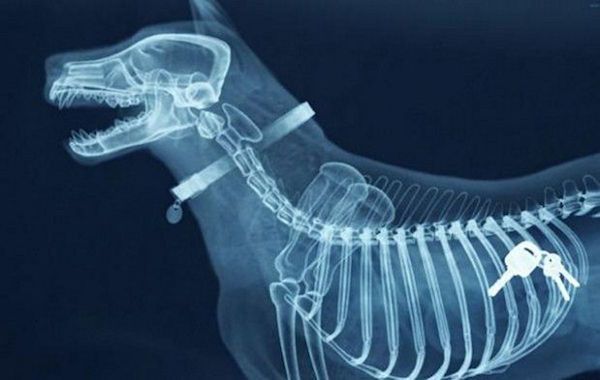

15 / 15Klucze

Obraz

© imgur.com

Jeżeli zabrał je panu na spacerze, to ciekawe jak się dostali do domu.